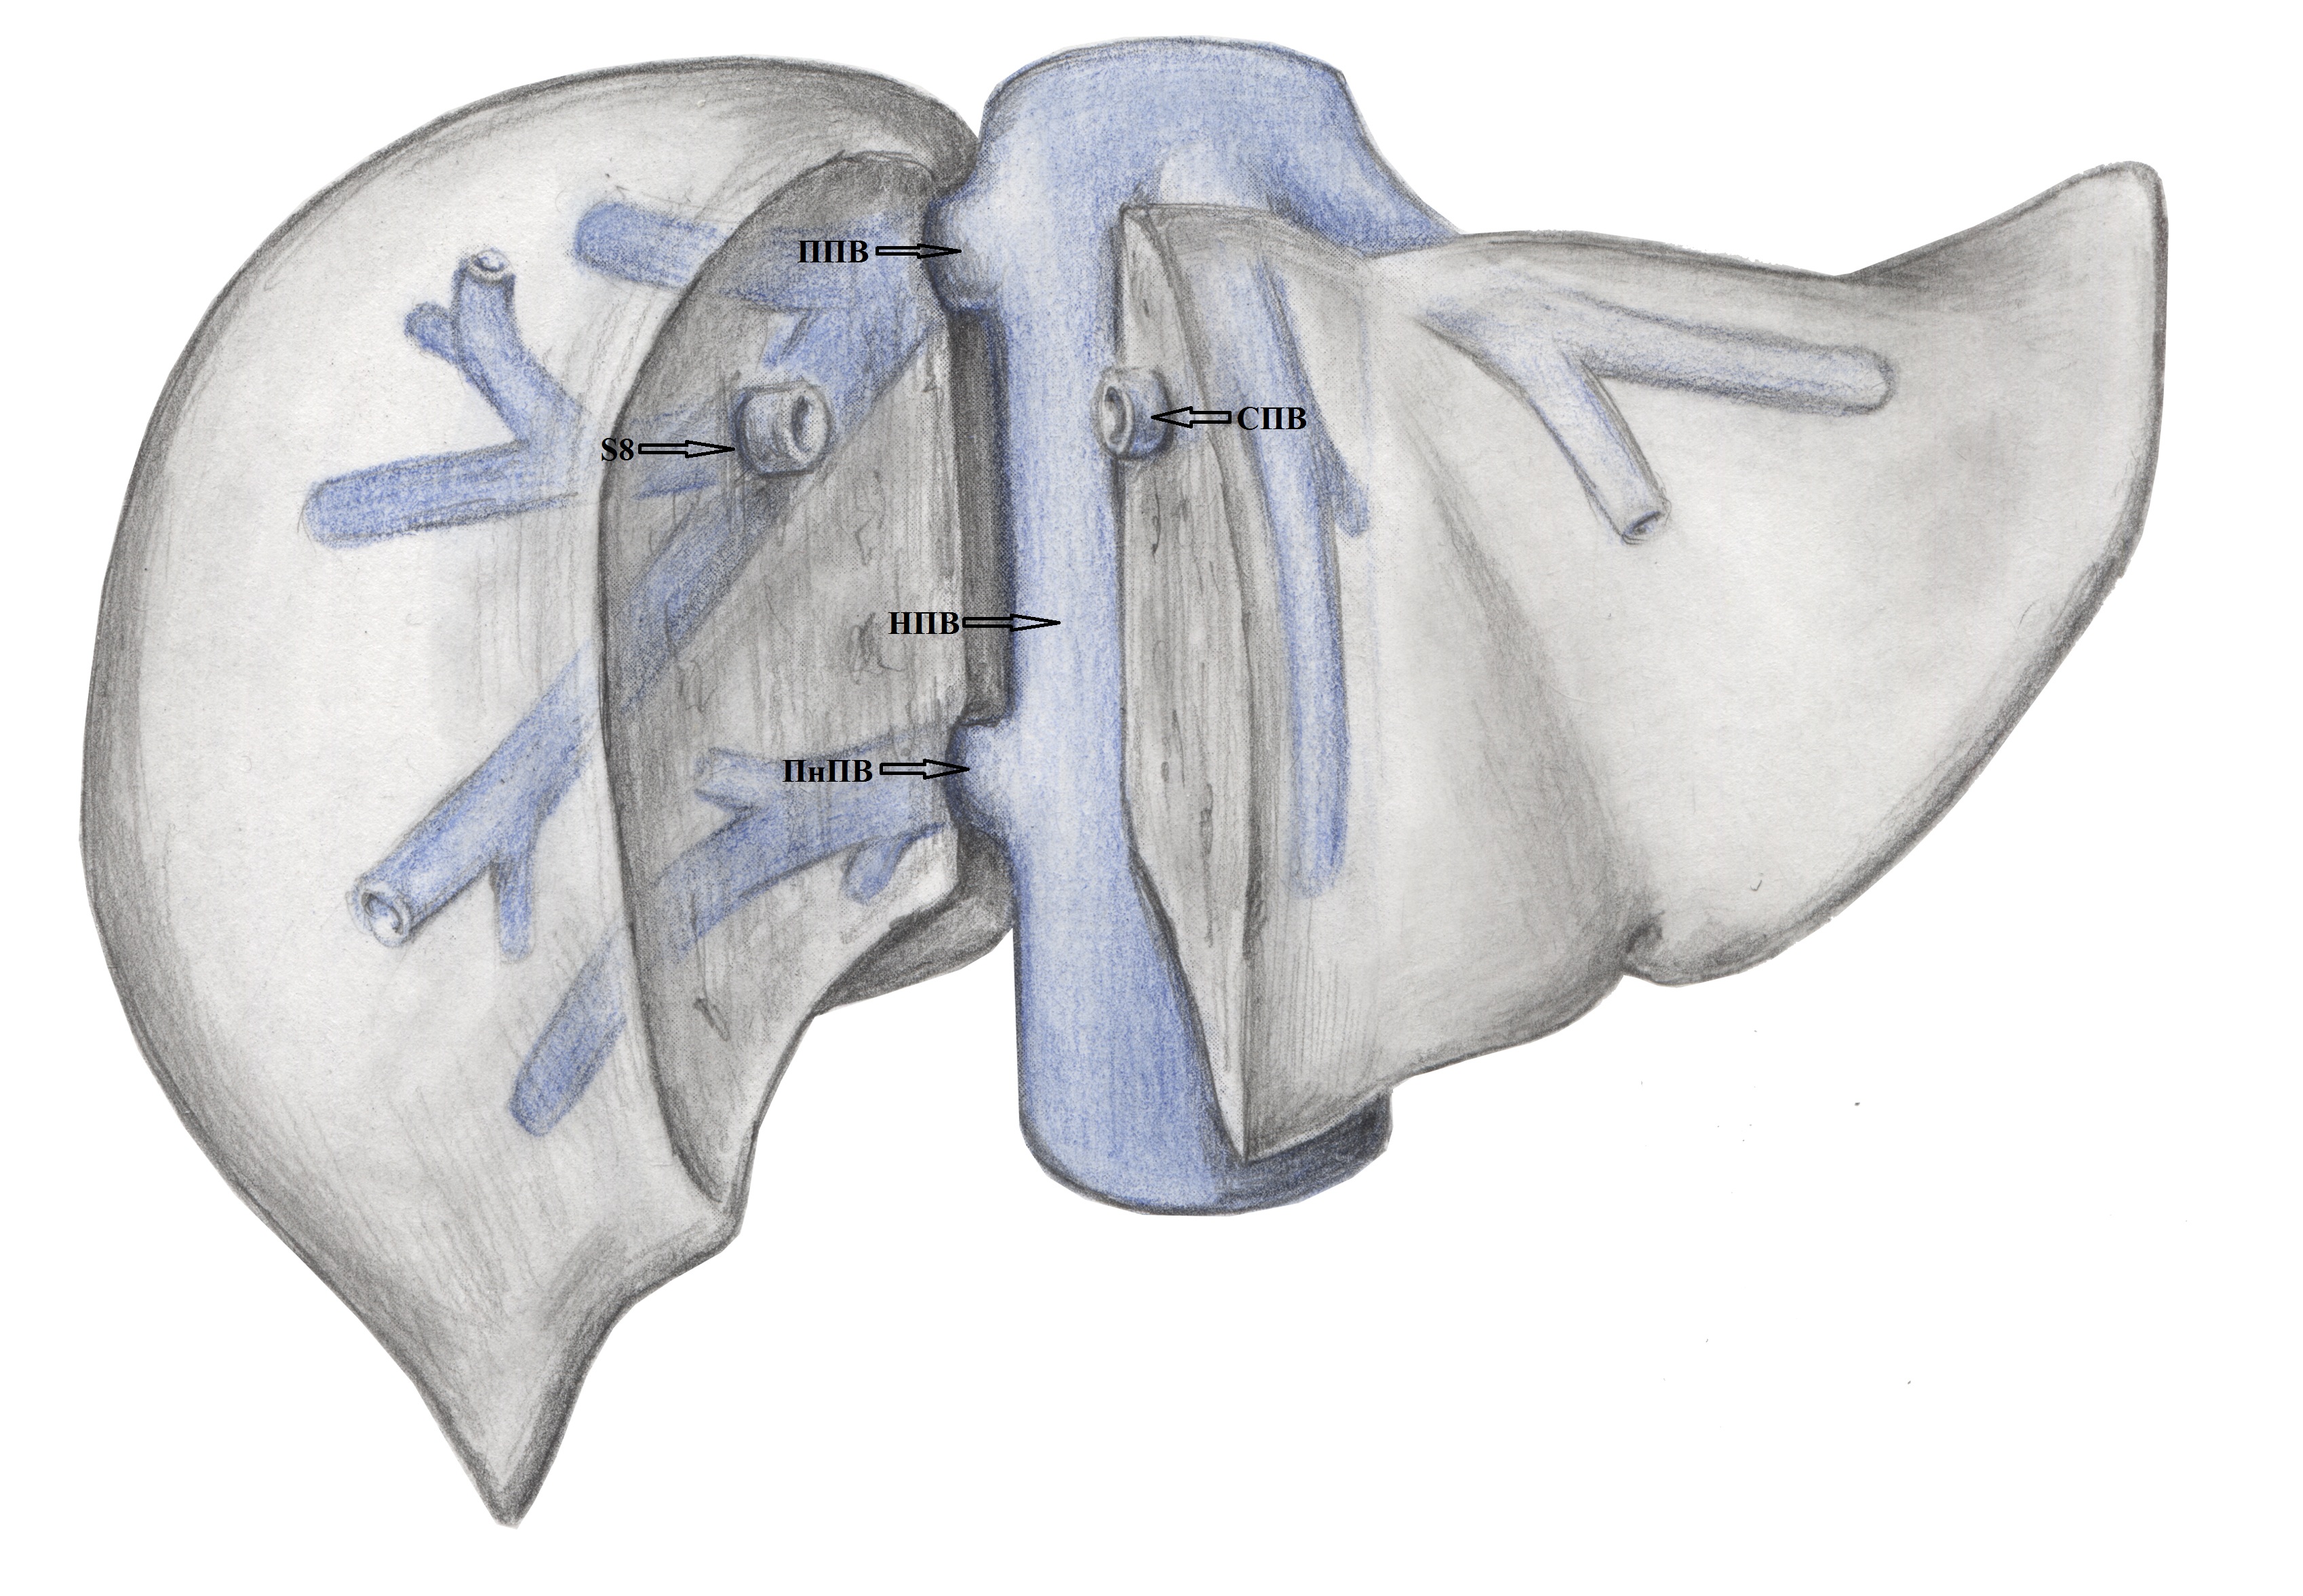

Результаты. Выявлено 14 подтипов анатомии эфферентных сосудов. Их классифицировали в 3 типа в зависимости от вклада срединной вены в отток крови от правой доли печени: кавальный (67,3%), кава-срединный (полусепаратный, 29%) и сепаратный (3,6%).

2. Тип А (схема). | |

| Тема | ||

| Тип | Исследовательские инструменты | |

Посмотреть

(1MB)

|

Метаданные ▾ | |

5. Тип B (схема). | |